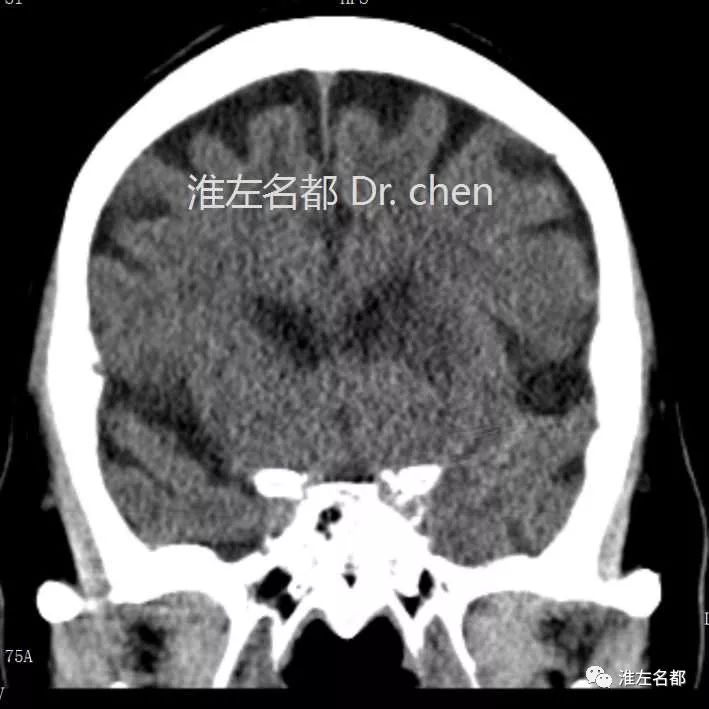

△CT平扫:左侧壳核前部稍低密度,边界模糊,

提示脑梗死。

△CT平扫:左侧壳核前部和尾状核头部低密度梗死灶,

蛛网膜下腔出血高密度已转为等密度。